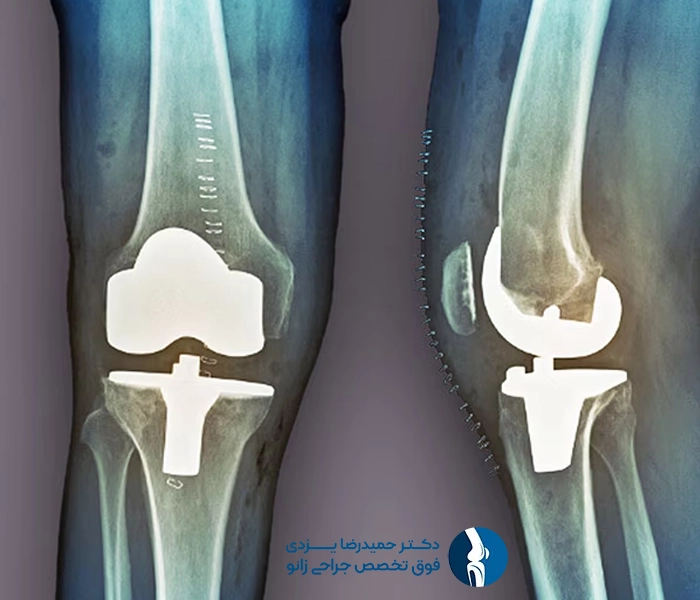

۱. پروتز کامل زانو (Total Knee Replacement)

در این روش کل سطوح مفصل زانو با پروتز جایگزین می‌شود. این نوع جراحی برای بیماران با آسیب گسترده مفصل مناسب است.

پروتزهای زانو معمولاً از ترکیب فلزات (مانند تیتانیوم یا آلیاژ کبالت-کروم) و پلاستیک‌های بسیار مقاوم (مانند پلی‌اتیلن) ساخته می‌شوند. این ترکیب دوام بالا، مقاومت در برابر سایش و حرکت روان را فراهم می‌کند.

۴. نصب پروتز

بخش‌های فلزی و پلاستیکی پروتز با استفاده از چسب استخوان یا روش‌های بدون چسب در محل قرار می‌گیرند.